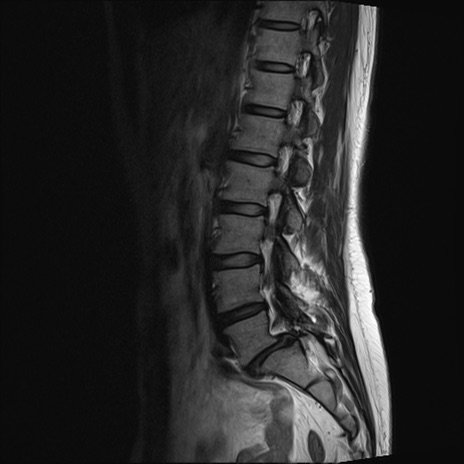

【整形】TIPS症例4 腰椎MRI T2WI(矢状断像)

腰椎MRI

T1WI(矢状断像)